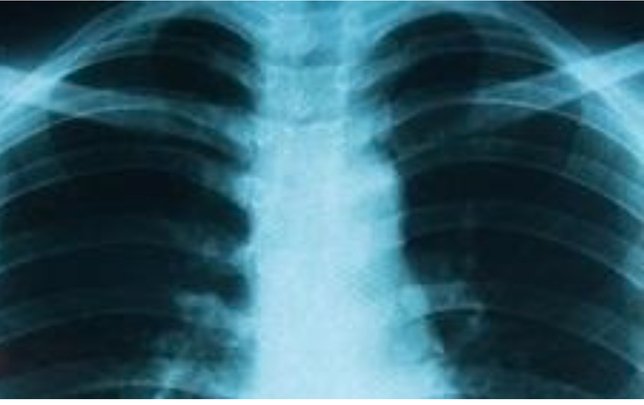

Para diagnosticarlo, los especialistas recurren a un conjunto de estudios clínicos que incluyen radiografías, tomografías, análisis de sangre y biopsias. Una vez confirmado, se determina su estadio, lo que permite diseñar un tratamiento adaptado a la extensión del cáncer y a las características del paciente.